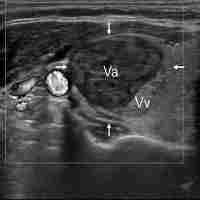

| Abstract | The use of Radiofrequency thermoablation (RFA) for treating large thyroid nodules is limited by the modest efficiency of the available systems in terms of volume of the ablation zones (AZs). This increases the risk of incomplete ablation of the nodule. Systems employing perfused electrodes have been developed to increase the volume of the AZ. Aim of this study is to compare the size of the AZ induced by RFA systems using internally cooled perfused vs. non-perfused electrodes in swine thyroids. RFAs were performed on 40 freshly isolated swine thyroids using both systems. The perfused system was tested using 0.9% saline, 7% and 18% hypertonic saline solutions. Energy delivery to the tissue was stopped when tissue conductivity dropped (real life simulations) and after an established time of 20 seconds (controlled duration). Following RFA, thyroids were transversally and longitudinally cut. Photographs were taken for macroscopic morphometry of the ablated zones before and after formalin fixation, to evaluate tissue shrinkage. Microscopic morphometry was performed on PAS stained sections. In real life simulation experiments, gross morphometry revealed that AZs produced with electrodes perfused using 7.0% saline are larger compared to isotonic saline. Microscopically, all the conditions tested using the perfused system produced larger AZs compared to non-perfused system after 20 seconds of RFA. In conclusion, the perfusion with 7.0% NaCl solution increased the electrical conductivity of the tissue in real life simulations, resulting in larger ablated areas compared to the use of isotonic saline. |